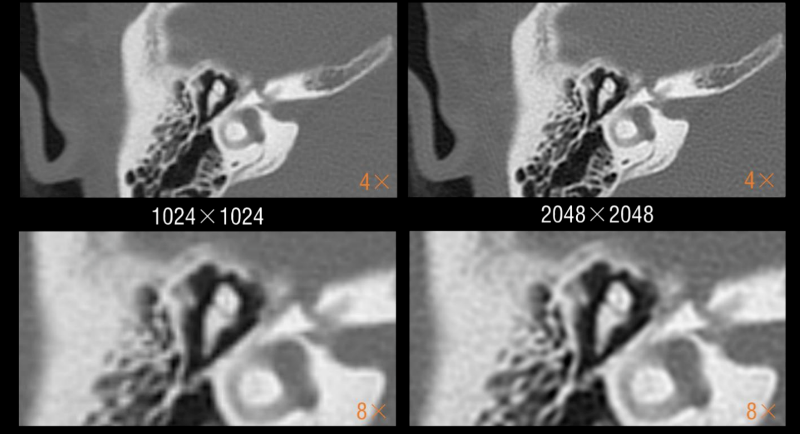

该设备集 “超高清成像、低剂量防护、极速扫描”于一体,将为辖区居民提供更精准、更安全、更便捷的诊断服务,标志着石岩人民医院在医学影像领域的诊疗水平迈入新阶段。 作为临床诊断的 “眼睛”,ANATOM X980的三大核心功能,直击患者就医痛点与临床诊断需求。 人性化设计与智能定位系统 ANATOM X980配备80厘米宽大机架孔径,结合舒缓氛围灯光,有效缓解患者检查时的紧张情绪。 设备搭载四块大尺寸高清触控屏,方便技师多角度掌握患者信息与设备状态,并可通过按键与无线遥控实现灵活摆位,大幅降低操作负荷,提升检查效率。 利用深度双目视觉认知系统,采用深度学习方式,赋予设备认知能力和行为,使系统能智能识别人体多个定位点,并在智能触屏终端上显示扫描部位,同时还能够自动识别拟扫描部位的等中心位置,实现精准化、智能化的患者摆位。 宽体探测器与极速扫描能力 依托16厘米宽体探测器结合0.25s的扫描速度,可实现全器官一站式扫描。 ▲ 心脏冠脉、主动脉、肺动脉联合扫描 通过AccuGating门控触发技术和 Adose mA电流调制技术和全新的算法、领先的AI成像技术手段,结合一键冠脉提取及分析、IVUS 模拟血管内超声、斑块分析、心功能分析、钙化积分分析、血管内窥镜、CT-FFR 技术,为患者带来了高成功率、高舒适度的单心跳(One-beat)心脏冠脉(CCTA)检查体验。 ▲ 心率103bpm 得益于一次单圈旋转最大16cm的覆盖范围,结合0.25s 的极快速度和安科独创的4D图像重建技术,在充分保证整个器官的各个位置数据的同时、同源、同向的条件下,实现了自由呼吸模式的肺部检查,为幼童、意识不清等患者肺部检查提供了最佳检查方式,为分析结果和治疗决策的准确性提供了保证。 高清影像与低剂量技术 ANATOM X980采用了基于深度学习技术的Artist 高保真图像降噪算法来对低剂量图像进行优化和处理。 与其他的算法相比,Artist 可以实现更彻底的噪声与图像信号分离,并确保在处理过程中图像细节信息不丢失,进而获得低剂量下高分辨的临床影像。 灌注扫描的剂量问题一直是临床中的老大难问题。ANATOM X980的超低mA采集及Artist还可在脑卒中解决方案中,可确保低剂量下获得精准的灌注数据。 此外,ANATOM X980还有其它几大独具特色的功能。 1.AI超分辨薄层重建技术(ASR) ANATOM X980搭载基于AI技术的高分辨率薄层图像重建技术(ASR=AI Super Resolution reconstruction),该技术利用神经网络处理单元通过深度学习的方式,对带有伪影的混叠投影数据进行伪影校正和重建,可显著降低混叠伪影,提高 CT 图像的分辨率,获得高分辨 0.3125mm 的超薄层图像,从而提高临床诊断准确性。 2.AccuImage 2048×2048显微成像 将图像数据量提高 16 倍,可显示和观察更多的病变影像细节。 3.AccuSpiral能谱成像 基于AI迭代重建与能谱解析技术,可定量分析组织成分,辅助肿瘤良恶性鉴别、结石成分分析及出血定位,为临床提供形态与功能融合的多维度信息。 目前,ANATOM X980 已在石岩人民医院影像科正式投入使用,从常规体检到复杂病症诊断,从成人检查到儿童诊疗,全方位满足临床需求。 石岩人民医院将以这台 “精准诊断利器” 为依托,持续提升诊疗能力,让居民在家门口即能享受到高质量医疗服务,用科技守护每一位居民的健康! 咨询电话 0755-27609000转0121 石岩人民医院放射科 石岩医院放射科现有医护42人,其中主任医师1名,副主任医师5名,中级职称24名,初级9名,助理技师、岗培各2名。 设备由数字化DR、CT、MR、DSA和骨密度仪等组成。中心设备齐全,拥有世界上先进的1.5T磁共振(MR)一台;螺旋CT3台(包括安科256排512层CT1台、安科64排128层CT1台、安科32排CT1台)。 数字减影血管造影机(DSA)1台;数字胃肠机1台;数字化DR和移动DR共6台;并配有现代化的PACS、HIS、肺结节和心脑血管AI辅助后处理诊断系统。 审核|梁雄 责编|马章林 审校|张永东 图文|郭文霞 编辑|冯丽萍 校对|吴曼莉